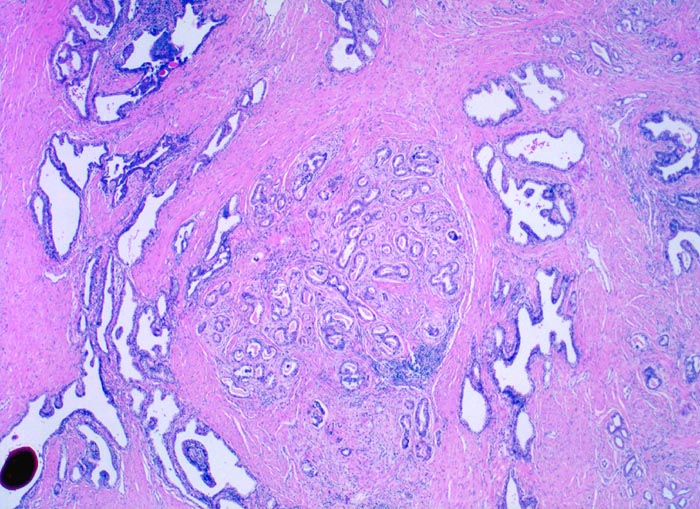

• Normale Prostatadrüsen mit grossen Lumina angeordnet in Läppchen. Das Epithel bildet Falten und besteht aus einer inneren hochprismatischen sekretorischen Zellschicht und einer äusseren Schicht flacher Myoepithelien.

• Herde kleiner Karzinomdrüsen ohne Basalzellschicht.

• Fehlende lobuläre Anordnung der Karzinomdrüsen.

• Konfluierende Drüsen bilden kribriforme Muster.

• Karzinomzellen mit stark erhöhter Kern-Zytoplasmarelation und hyperchromatischen Zellkernen mit grossen eosinophilen Nukleolen.

• Wenig differenzierte Karzinomanteile ohne erkennbare Drüsenbildung.

• Perineuralscheideninvasion.

• Links oben im Präparat finden sich Anteile der Samenblase mit polymorphem Epithel und gelben Lipofuszinpigmenteinlagerungen.

• Unterhalb der Samenblase sind von flachem Endothel ausgekleidete Lymphgefässe mit Karzinominfiltraten erkennbar (Lymphangiosis carcinomatosa).

• Der mit schwarzer Tusche markierte Resektionsrand in der unteren Hälfte des Präparates ist tumorfrei.